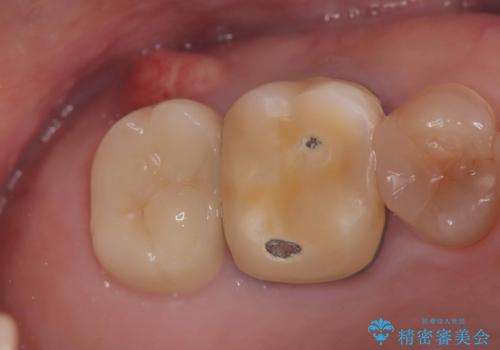

- 治療計画

- 右上7番に瘻孔を認め、根管治療を実施しましたが、瘻孔が再発し治癒が得られなかったため、抜歯のうえインプラントによる補綴治療を行いました。